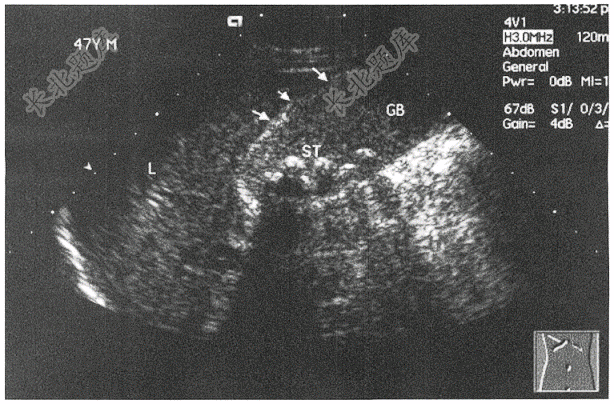

- 简答题患者,女,45岁,因腹痛就诊,行B超如下图,请进行简单描述和写出主要诊断